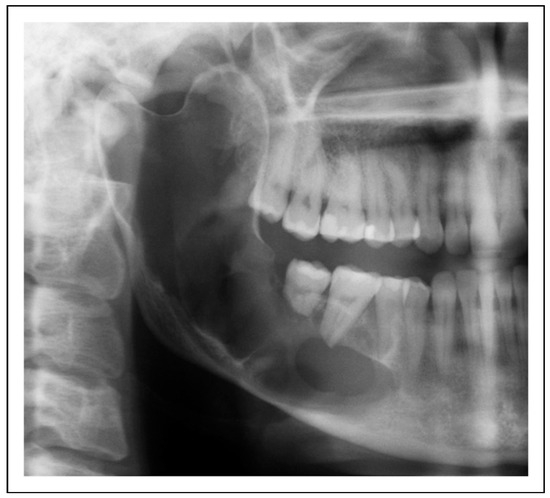

Bilateral TMJ Replacement With Complete Replacement of the Mandible, Patient 8